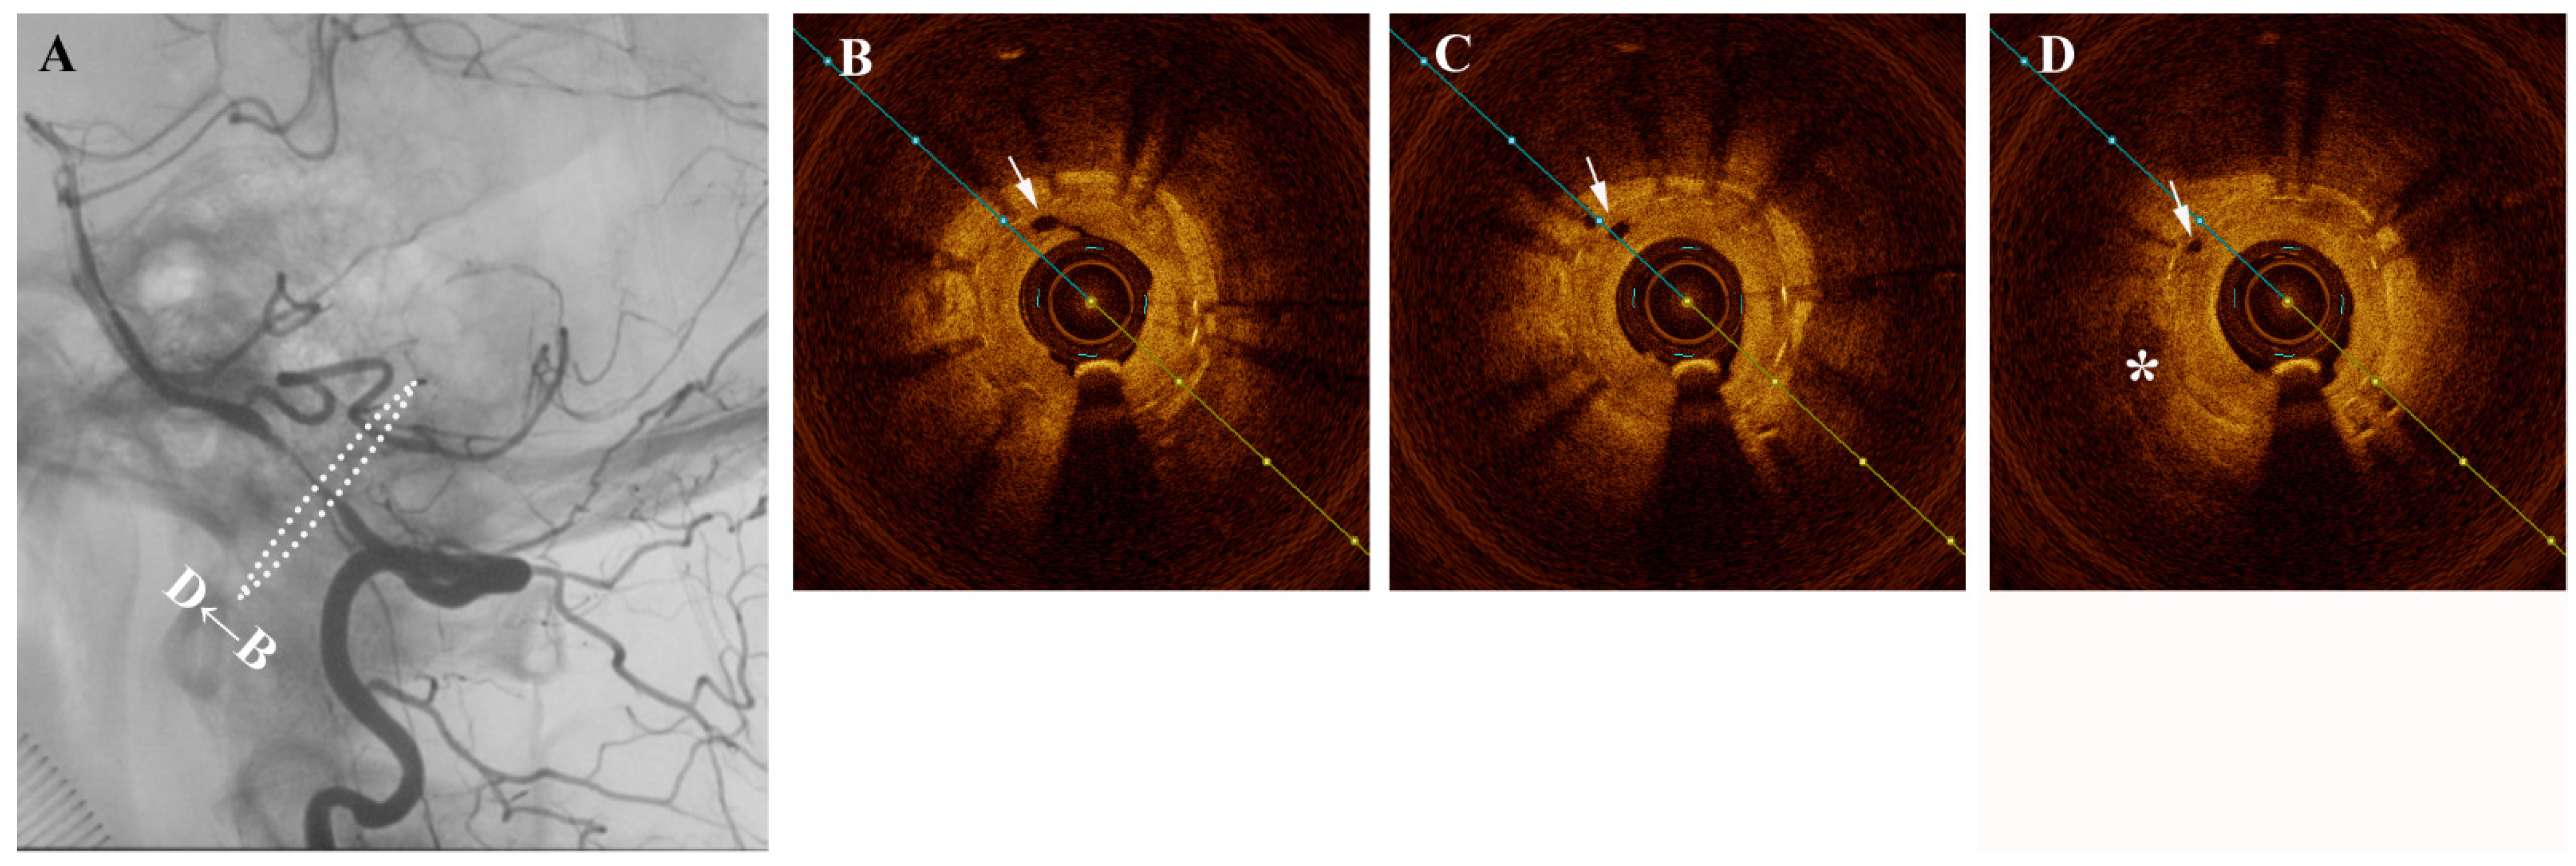

A middle-aged female presented one year after intracranial stenting for severe left intradural segment vertebrobasilar stenosis with recurrent vertigo. Digital subtraction angiography (DSA) confirmed severe in-stent restenosis and same-session optical coherence tomography (OCT) with an Ilumien Optis probe (St. Jude Medical, St. Paul, MN, USA) showed neovascularization-related neointimal hyperplasia (Figure 1). Figure 1 (A) Angiography confirming severe intracranial in-stent restenosis of the left intradural vertebral artery segment. Figure 1 (B–D) Pre-intervention cross-sectional optical coherence tomography (OCT) shows hypertrophic intima and hyporeflective microchannels (white arrow) originating directly from the lumen and penetrating contiguously towards the plaque (*). These are seen as hyporeflectile microchannels originating directly from the lumen, which penetrate contiguously towards irregular plaque and hyperplastic intimomedial complex. Neovascularization plays a role in intracranial atherosclerosis by providing trophic factors to plaque []. Such neovasculature is susceptible to intra-plaque hemorrhage and also importantly is a critical factor in the propagation of intimal hyperplasia following stenting []. Intracranial neovasculature cannot be resolved in-vivo by traditional imaging methods. In 2011, Mathews et al. performed OCT in the cavernous and the petrous segments of internal carotid artery, which used time-domain OCT assembled in a laboratory rather than a commercial product []. Although a small number of cases were enrolled, the result suggested that OCT examination of intracranial arteries was feasible. Until now, there have been numerous preliminary attempts at intracranial OCT use, but visualization of intracranial neovasculature has heretofore not been reported in a living patient. With the approximately 40 micron resolution afforded by OCT, an extremely rare and vivid look at the mechanisms behind plaque nutrition and neointimal hyperplasia of the intracranial vertebral artery is possible []. The in-stent stenosis was treated a Sequent Neo paclitaxel-coated balloon (B.Braun, Melsungen, Germany) for intimal hyperplasia inhibition (Figure 2). As plaque and neointimal morphologic characteristics are increasingly recognized as important contributors to disease prognosis and natural history, OCT may stand to inform treatment decisions and assess intimal tearing in the future.

Figure 2.

(A) Angioplasty with a drug-coated balloon was performed to recanalize successfully without significant intimal tear (B–D).